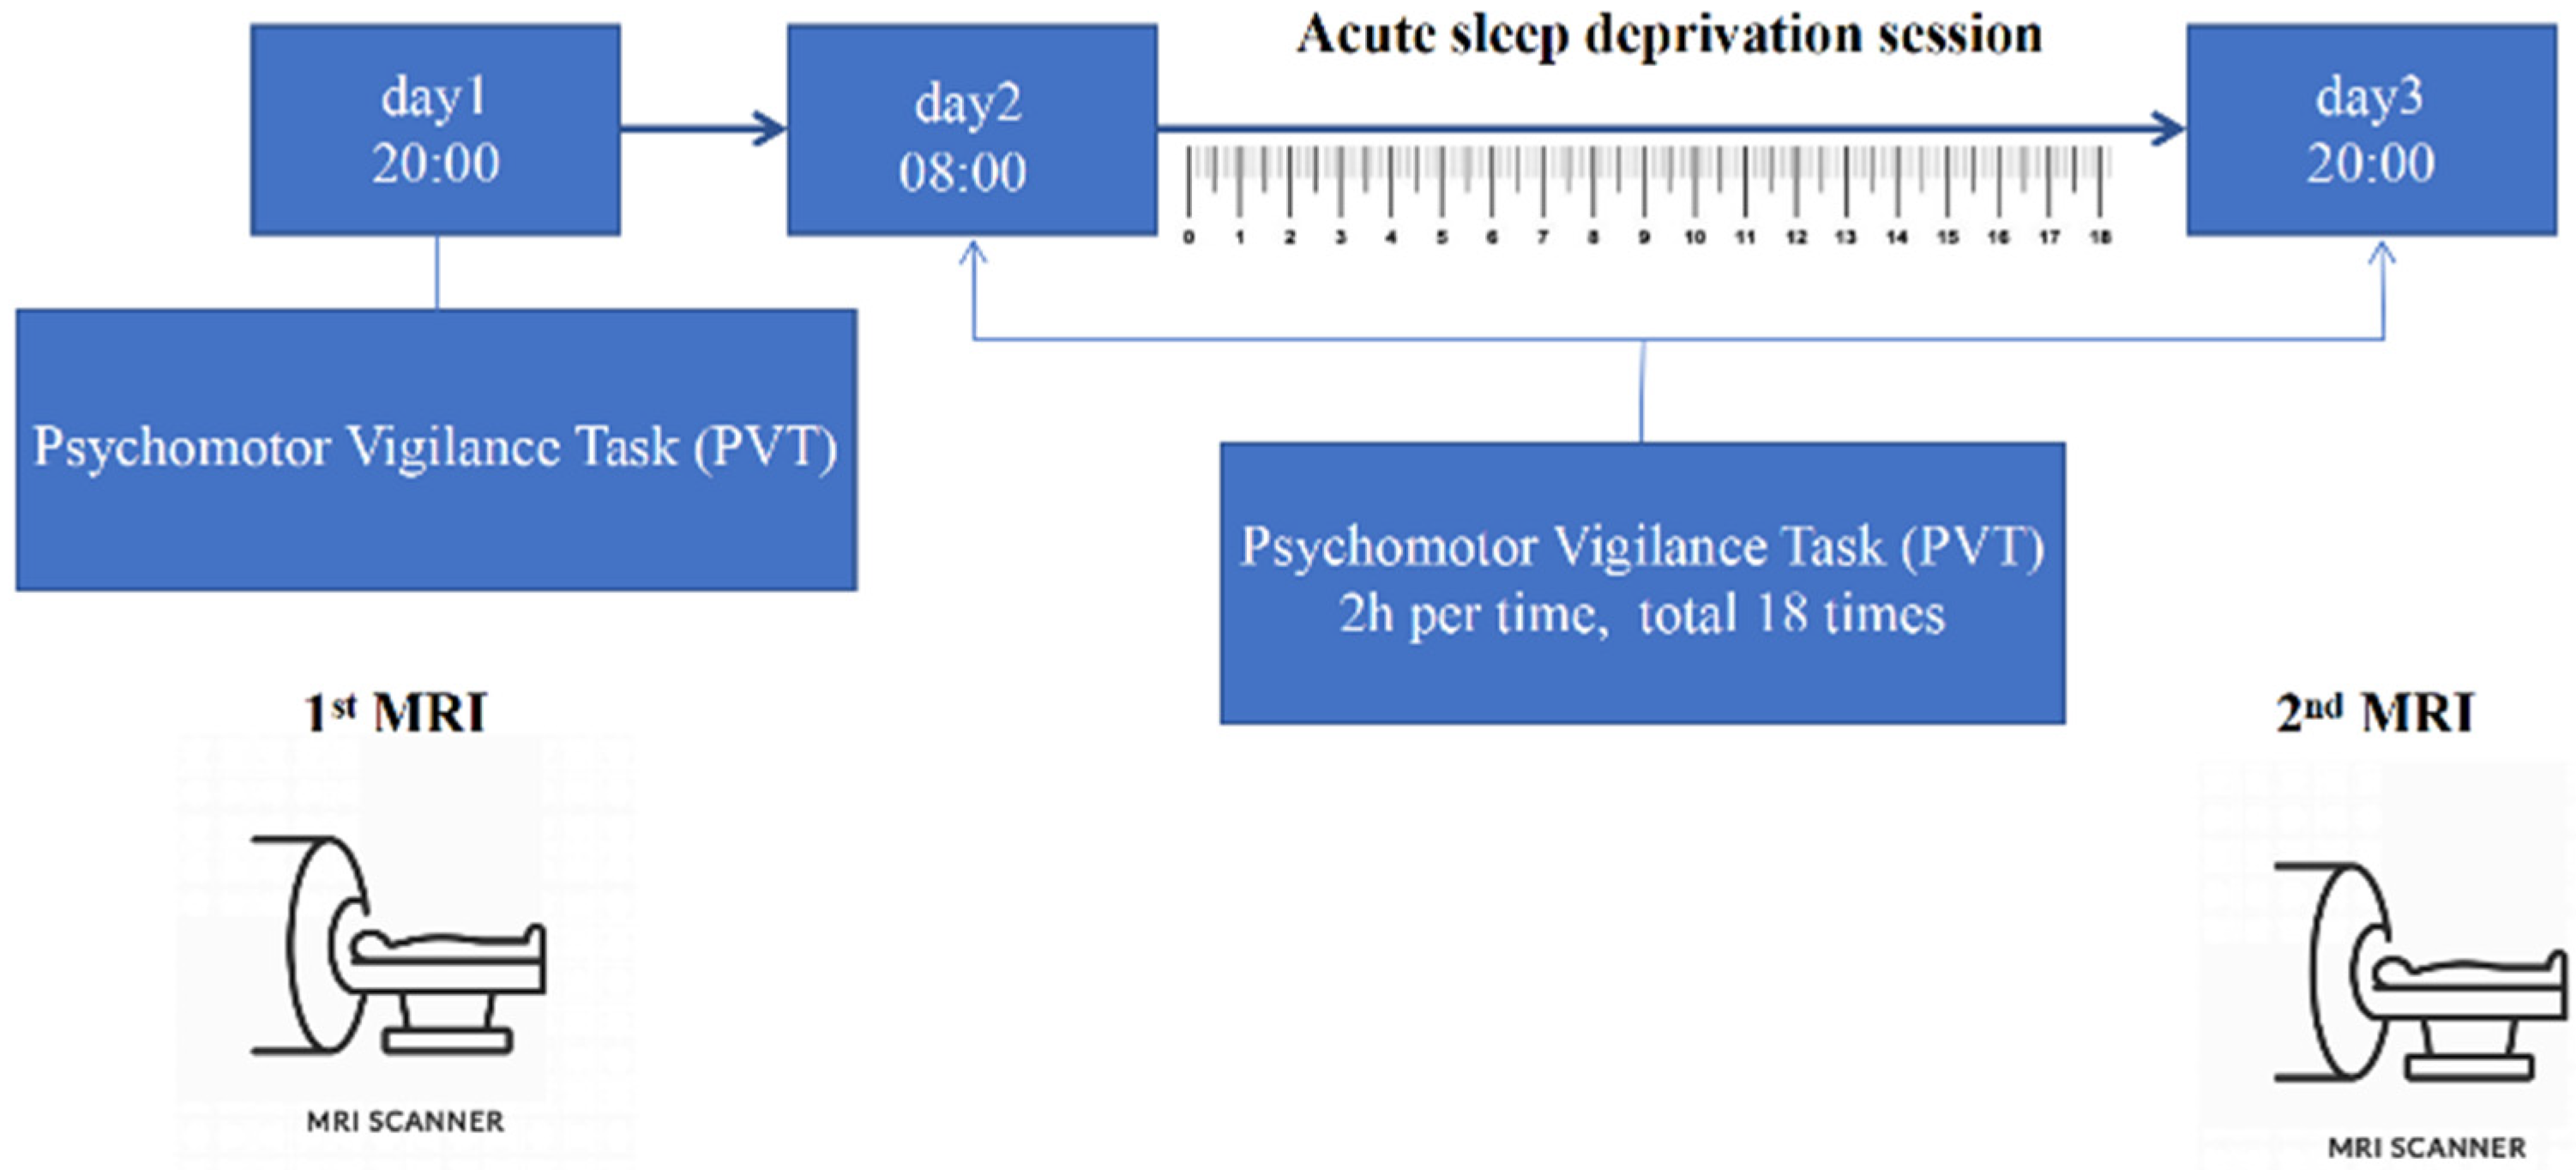

2.2. Experiment Paradigm

2.3. MRI Data Acquisition